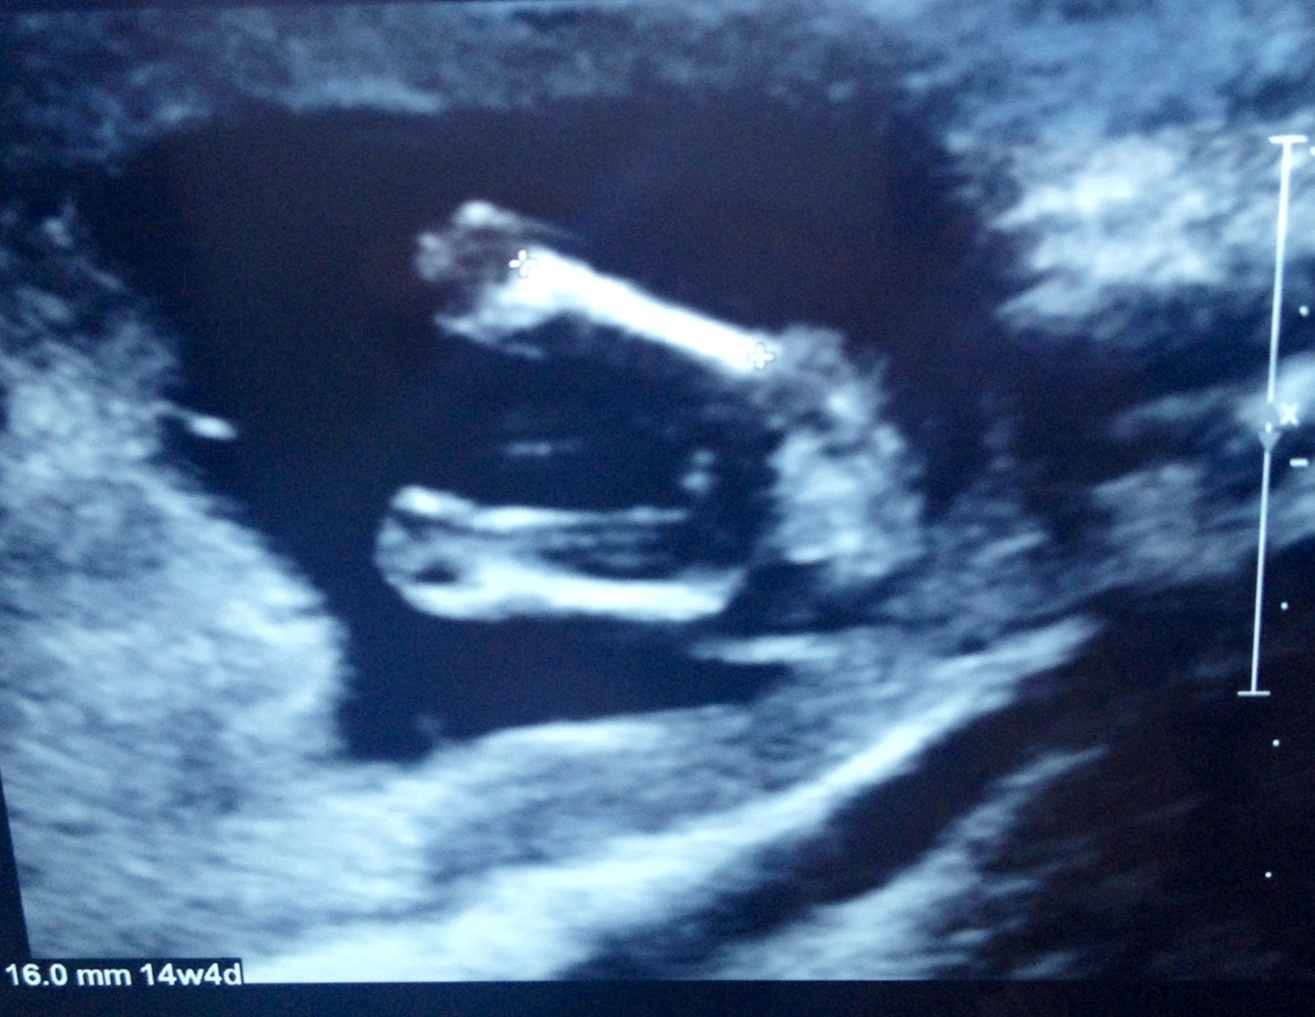

Hi ladies, had my scan today and tech clearly showed me 3 lines and then said not to get set on having a girl till my 20 week confirmation!!! What do you all think tho? Did anyone have a boy potty shot like this at 14 weeks 5 days?

Attachment 12848Attachment 12849